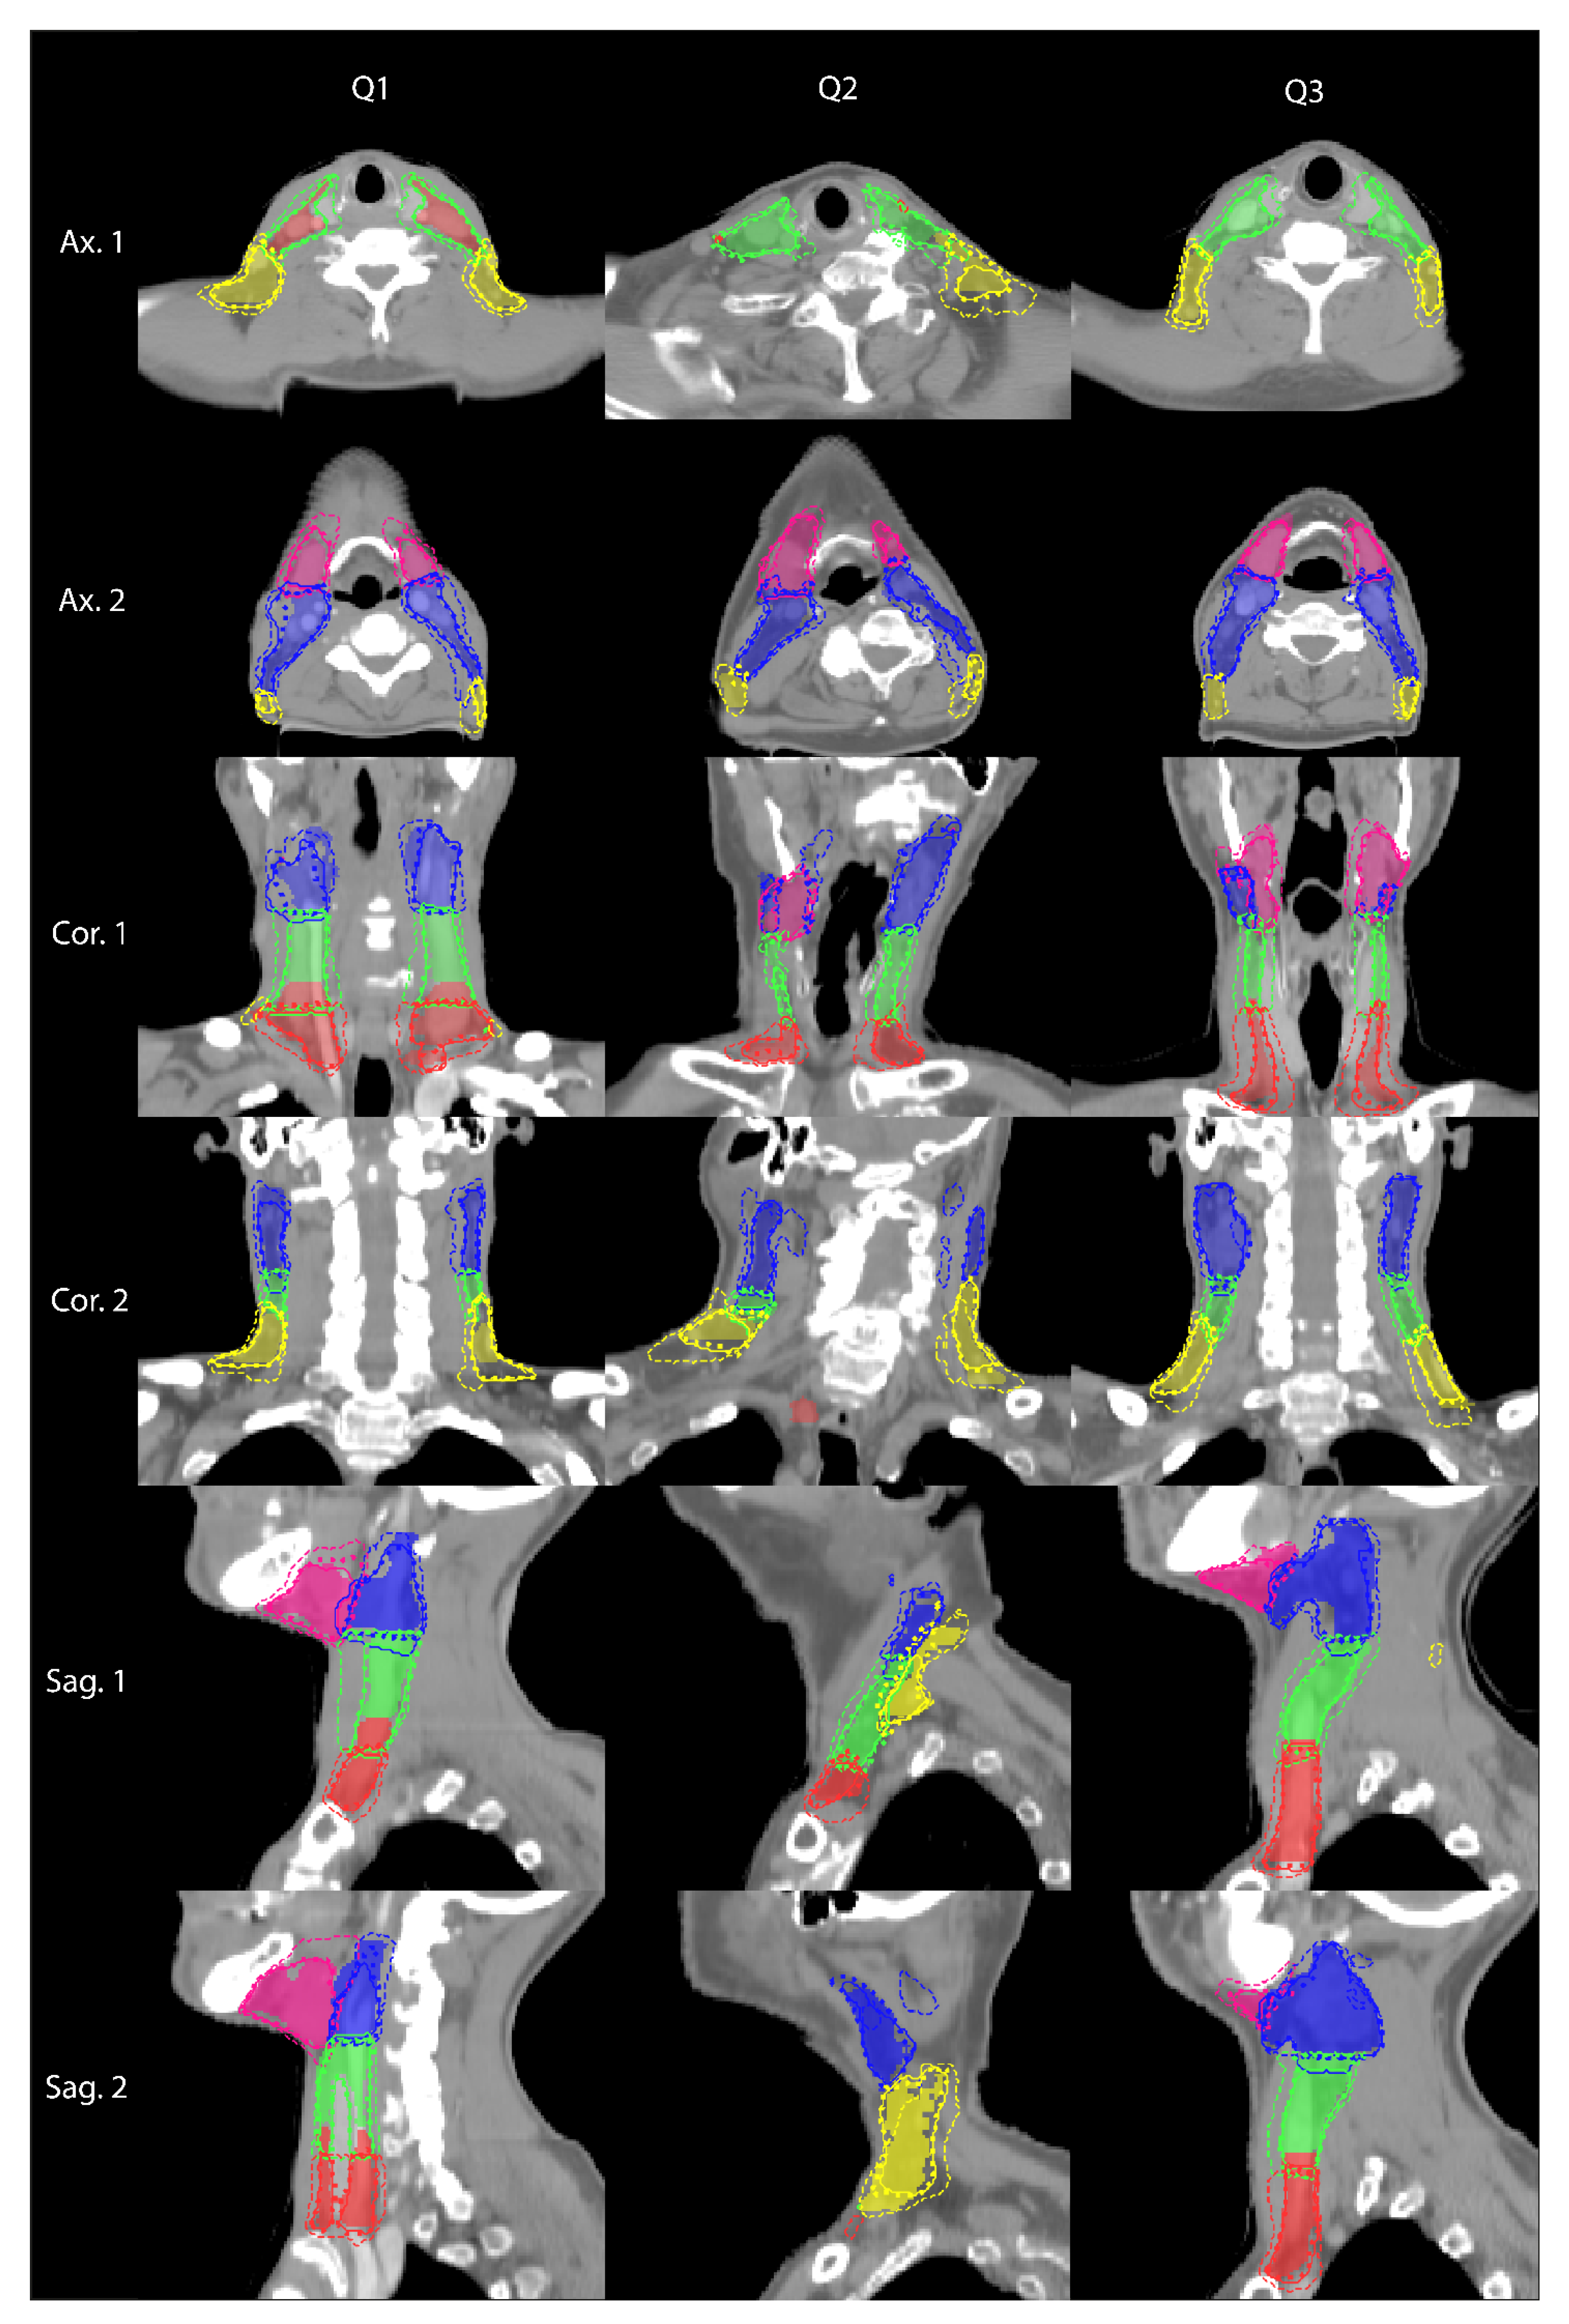

3. Results

4. Discussion